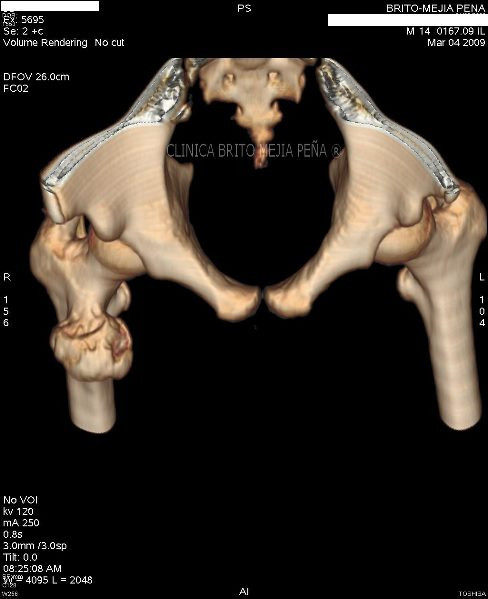

Pié normal anterior